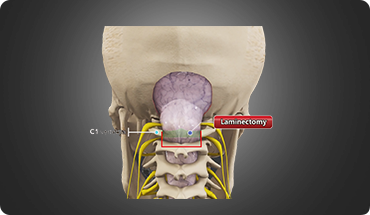

Degenerative Spinal Conditions

A degenerative condition is a continuous deterioration of a tissue or an organ in your body over time.